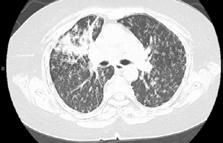

A 58-year-old female with recently diagnosed COVID-19 pneumonia was found to have a dry cough and dyspnoea in the setting of persistent bilateral hilar and mediastinal lymphadenopathy associated with bilateral nodular infiltrates. Of note, she immigrated to the USA from India 10 years prior, with the most recent travel to India 2 years ago. Quantiferon testing upon return to the USA was negative at that time. Workup included bronchoscopy with endobronchial ultrasound revealing non-caseating granulomas with negative stains for acid-fast bacilli (AFB). She was diagnosed with Stage 3 sarcoidosis and initiated on prolonged steroid taper with improvement of symptoms. With taper of steroid dose, however, she developed lymphocyte-predominant exudative effusion with negative cultures, and was reinitiated on a protracted steroid course with rapid symptom resolution. At 4-month follow-up, she had worsening CT findings upon steroid taper, and was started on azathioprine. One month later, she required hospital admission for worsening dyspnoea and fatigue. She was noted to be febrile, tachycardic, and tachypnoeic with worsening

hypoxia. Subsequent CT chest showed progression of bilateral nodular infiltrates with new right upper lobe consolidation and air bronchograms concerning for multifocal pneumonia (Figure 1). Incidentally, she was also noted to have calcified splenic granulomas. She developed rapid clinical deterioration, ultimately requiring mechanical ventilation, pressor support, and continuous renal replacement therapy. Repeat bronchoscopy revealed diffuse alveolar haemorrhage with multiple AFB smears positive for Mycobacterium tuberculosis. She was immediately initiated on quadruple therapy, but unfortunately, despite treatment, developed refractory shock and passed away 2 weeks after initial presentation.

A) Initial adenopathy with peripheral patchy ground glass opacities in the right lung following COVID-19 pneumonia. B) Persistent bulky adenopathy 1 year after initial presentation. C) Extensive nodularity throughout the right lung with increasing confluent opacities in the right upper lobe and stable mediastinal lymphadenopathy 2 years after initial presentation. D) Tuberculosis superimposed on sarcoidosis with progression of nodular infiltrates, worsening right upper lobe consolidation, and air bronchograms with incidental calcified splenic granulomas (not pictured).

Figure 1: CT progression of patient’s sarcoidosis and tuberculosis.